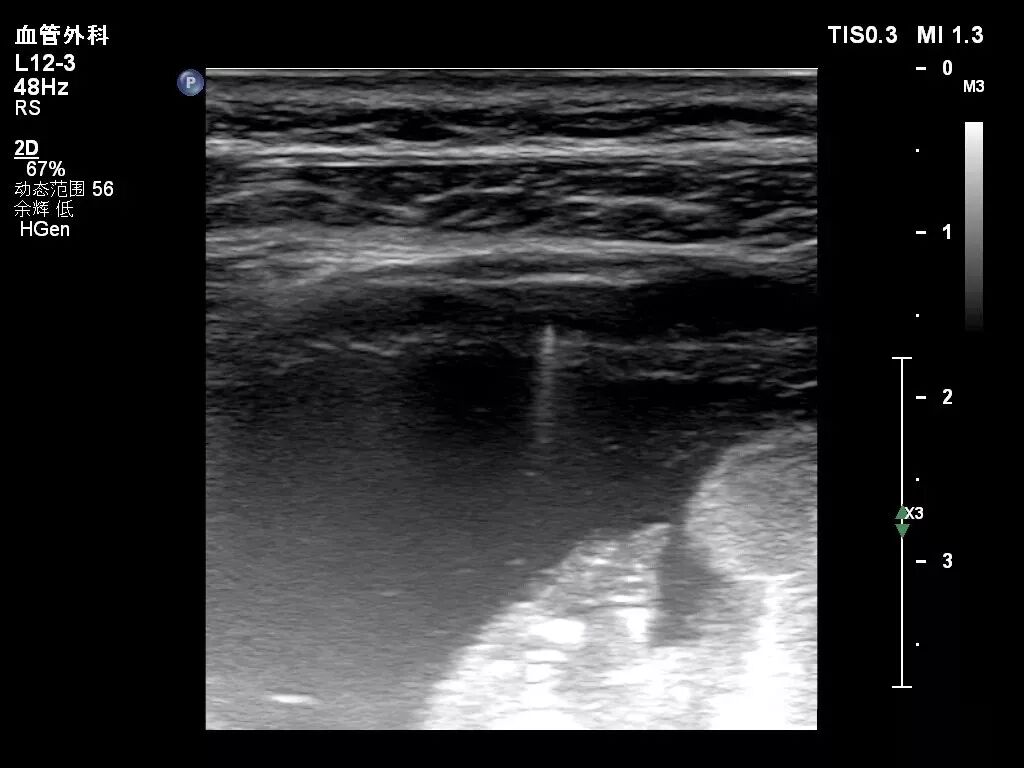

声影

声影是较常见的伪像之一,其发生是因为在超声扫描成像中,当声束遇到强反射(如含气肺)或声衰减程度很高的物资(如瘢痕、结石、钙化等)时,声束被完全遮挡而在其后方出现条带状无回声区即为声影。

声影对识别瘢痕、结石、钙化和骨骼时很有帮助。